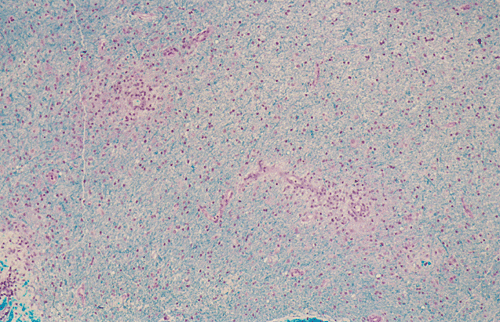

Streotactic biopsy yielded several cores of tissue. On scanning magnification, there are multiple small lymphocytic collections (Ž in Panel C) in the white matter. On higher magnification, these areas contain mostly lymphocytes without atypia. These collections appear to be angiocentric and are often admixed with some foamy macrophages (Panel  D and E). On LFB/PAS stain, multiple small, irregular areas of angiocentric pale staining are present (Panel F and G). On high magnification, these areas are featured by infiltration by foamy macrophages and lymphocytes and myelin loss (Panel  H). On Bielschowsky stain, the axons in these pale areas are largely preserved. Immunohistochemistry on GFAP demonstrates multiple stellate reactive astrocytes (Panel J). The macrophages and lymphocytes are also well demonstrated by immunohistochemistry for CD68 and LCA respectively (Panel  K and L).

The histopathology of inflammatory demyelinating pseudotumors is very similar to that of acute disseminated perivsnous encephalomyelitis or the classic type of ADEM. In essence, there is perivenous chronic inflammatory cell infiltration accompanied by infiltrating, foamy macrophages with an angiocentric distribution. Loss of myelin and relative preservation of axon fibers must be demonstrated before a diagnosis of demyelinating process is made. The loss of myelin can be well demonstrated by special stains for myelin with the Luxol fast blue based stains as one of the most commonly used stains. Relative preservation of axons can be sell demonstrated by silver stains such as Bodian stain, Bielschowsky stain, and also immunohistochemistry for moderate and high molecular weight neurofilament proteins. The pathologic highlights on separating inflammatory demyelinating lesions from mimicking lesions have been well described by Zagzag et al. 8. Other inflammatory lesions, particularly viral infectons, must also be ruled out. Keen observations particularly for nuclear inclusion bodies, immunohistochemistry for specific viral agents, and laboratory studies of the cerebral spinal fluid (CSF) and blood are often helpful. Identification of oligoclonal bands on electrophoresis of CSF is a strong suggesting of a demyelinating process.